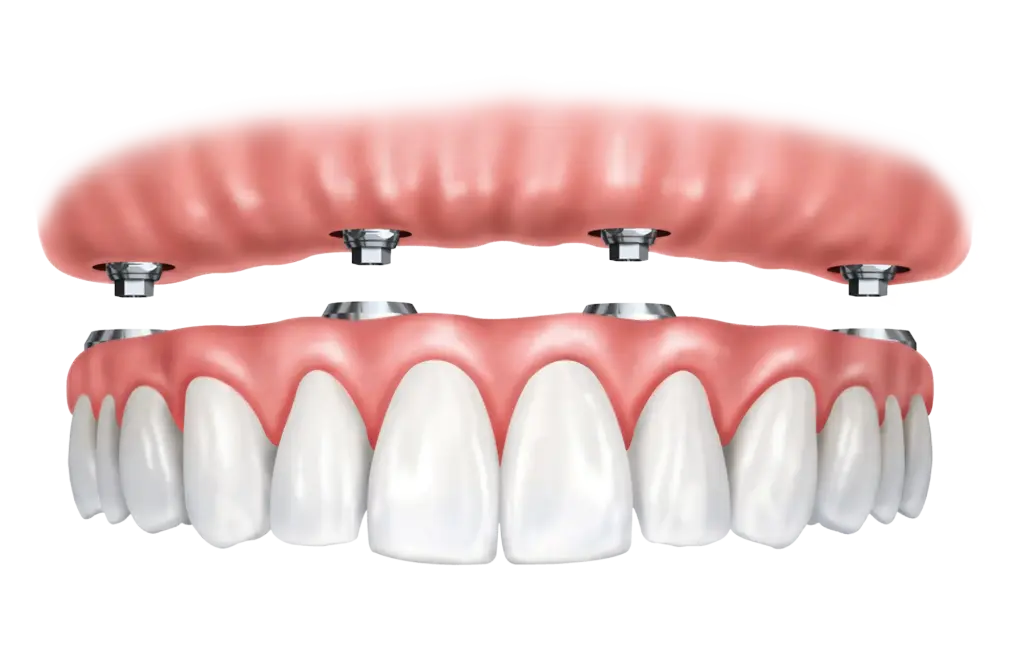

Prótese Protocolo

A prótese protocolo é uma solução moderna e definitiva para quem perdeu todos os dentes de uma arcada. Fixada sobre implantes dentários, ela oferece mais segurança, estabilidade e conforto em comparação às dentaduras tradicionais.

- Estética natural e harmônica

- Mais firmeza ao falar e mastigar

- Recuperação da autoestima e da qualidade de vida

- Facilidade na higienização

- Tratamento duradouro e previsível